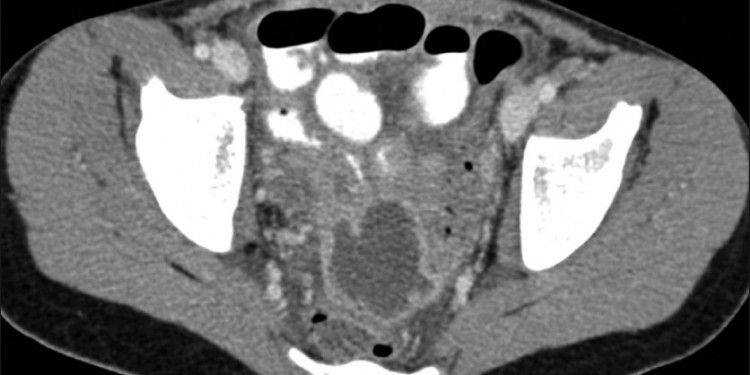

Kırk altı yaşındaki bayan pelvik cerrahi sonrası geçmeyen, azalmayan, dirençli karın ağrısı ile acil servise başvuruyor. Hastanın bir hafta önceki batın tomografisinin normal raporlandığını öğreniyorsun ama radyoaktif komplikasyonları göze alarak hastanın pelvisini kontrastlı tomografi ile görüntülüyorsun ve gördüklerini aciltıp.com senden istiyor.

Pelvis apsesi uzun süre tedavisiz kalan hasta ilk kalça nakli ile ödüllendiriliyor ve literatüre geçiyor.